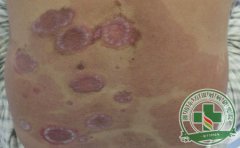

牛皮癣是很常见的一种慢性皮肤病,发病后会给我们造成极大的危害。因此,我们要在发现后及时去医院治疗,以免病情恶化,诱发其他疾病。调查发现,很多患者都在担心牛皮癣会传染,为什么很多人对牛皮癣传染心存疑惑呢...[详细]